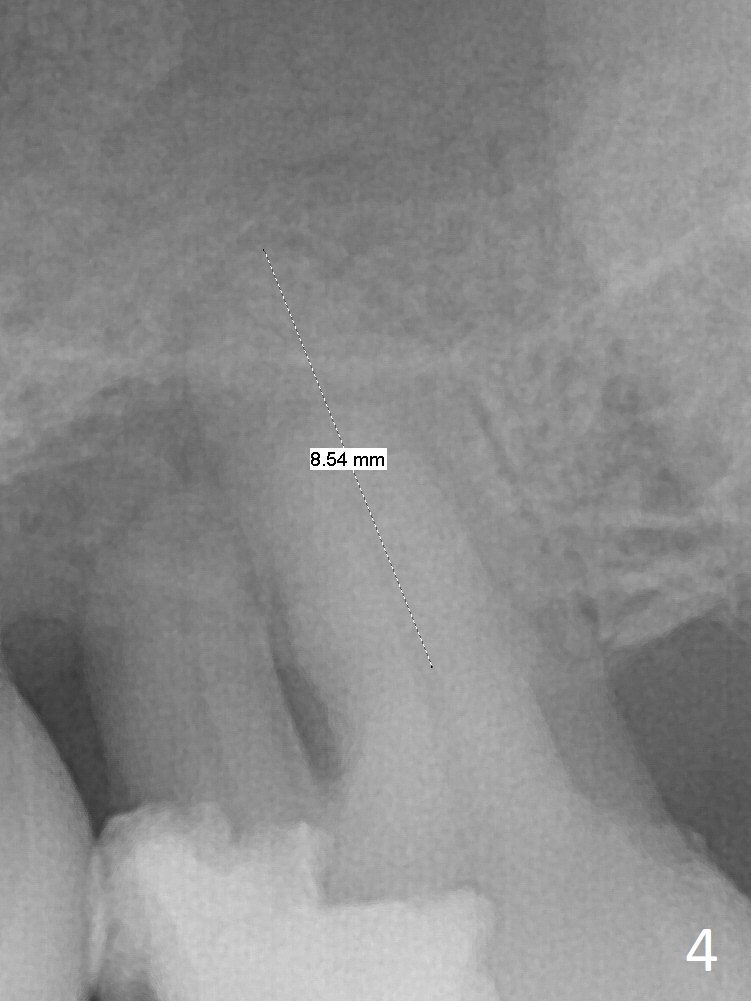

Bone loss seems to be the most severe around the mesiobuccal root (Fig.2 *), from which the osteotomy should stay away (Fig.3).  It may be the safest to place an implant in the palatal socket, leaned as buccally as possible so that the coronal end of the implant will be in the center of the extraction socket.  Re-measure the palatal socket length from PA and Pan: 8.5 and 10 mm, respectively.  The implant length should be around 10 mm.  Place bone graft before the final tap and take X-ray.